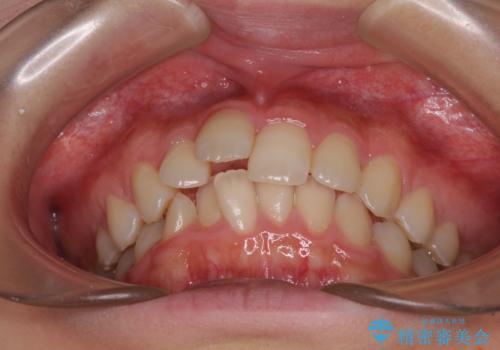

- デコボコした前歯をセラミックできれいに揃えたいとのことで来院された患者様です。

歯を削って整えることは簡単ですが、健全な歯を削って後悔してからでは遅いため、矯正治療を提案しました。

はじめは矯正治療の期間が長いことに悩んでいらっしゃいましたが、ある程度整えば満足するだろうとのことで、インビザラインにて矯正治療を行うこととしました。

左上の犬歯が欠損しているため、正中の位置や奥歯の咬み合わせが理想的にならない点を了承していただきました。